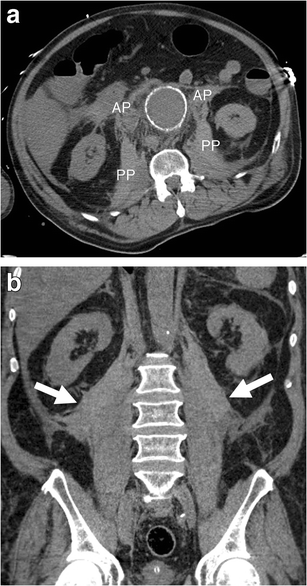

Retroperitoneal haematoma. a Axial unenhanced CT image of a 72-year-old man demonstrates haemorrhage involving bilateral anterior (AP) and posterior (PP) pararenal spaces as well as the area along the psoas muscles. The left kidney is displaced laterally. Attenuation of 45 HU (more than 30 HU) indicates acute haematoma. b Coronal unenhanced CT image of the same patient shows bilateral retroperitoneal haematomas (white arrows)